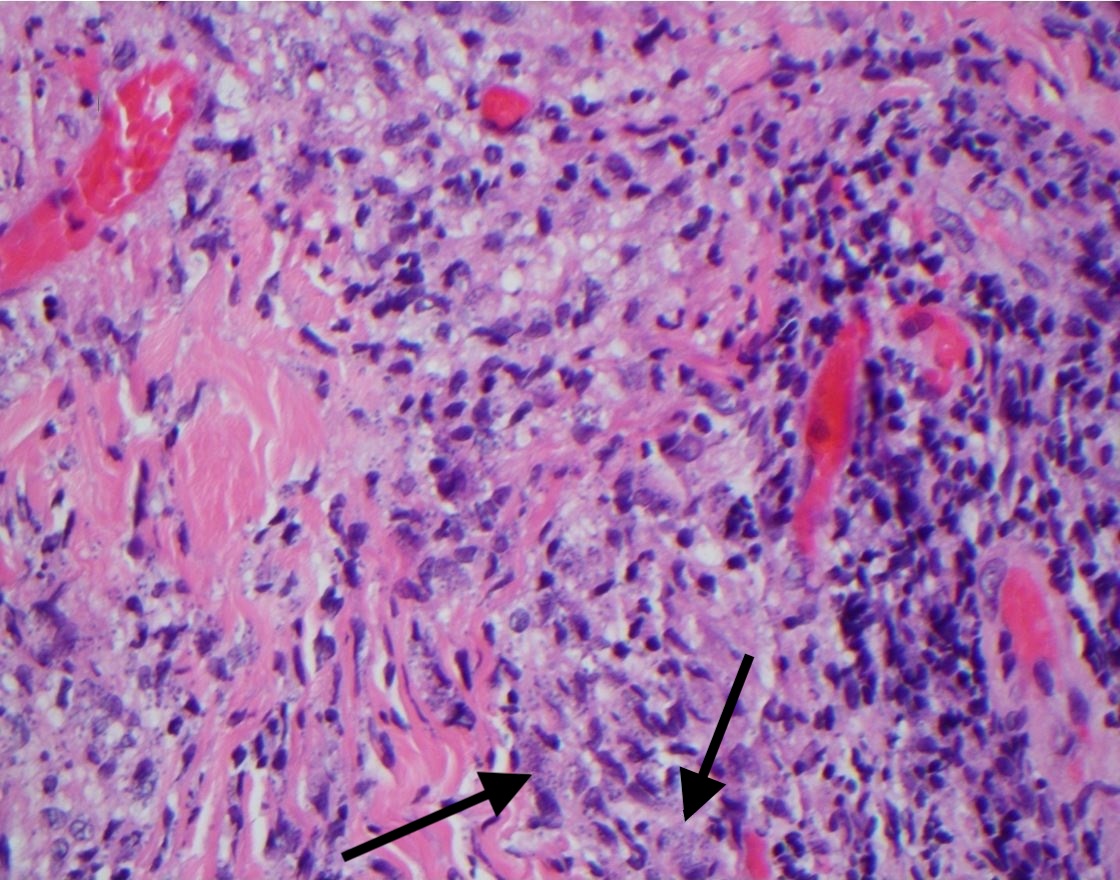

Results of a punch biopsy demonstrated multiple microorganisms (Leishmania amastigotes) within the dermal histiocytes (Figure 3) with negative acid-fast bacilli (AFB) staining results and negative cultures for aerobes, anaerobes, and fungi.

Figure 3. Histology results of a punch biopsy specimen showed Leishmania amastigotes in the dermal histiocytes (arrows).Discussion. Localized cutaneous leishmaniasis is a disease caused by the protozoan parasite Leishmania.1-3 The distribution is divided into Old World (Eastern Hemisphere, with the widest distribution in the Middle East, Mediterranean littoral, Arabian Peninsula, Africa, Indian subcontinent, and other areas)2,3 and New World (Western Hemisphere, typically in South America, Central America, and parts of Mexico)3 based on the distribution of species of Leishmania.